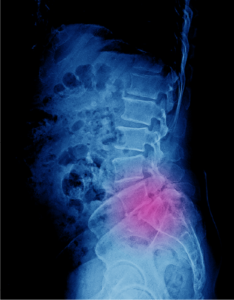

Vertebral Compression Fractures

Back pain is an indication of stress fractures known as vertebral compression fractures. Vertebral compression fractures occur when the normal vertebral body…